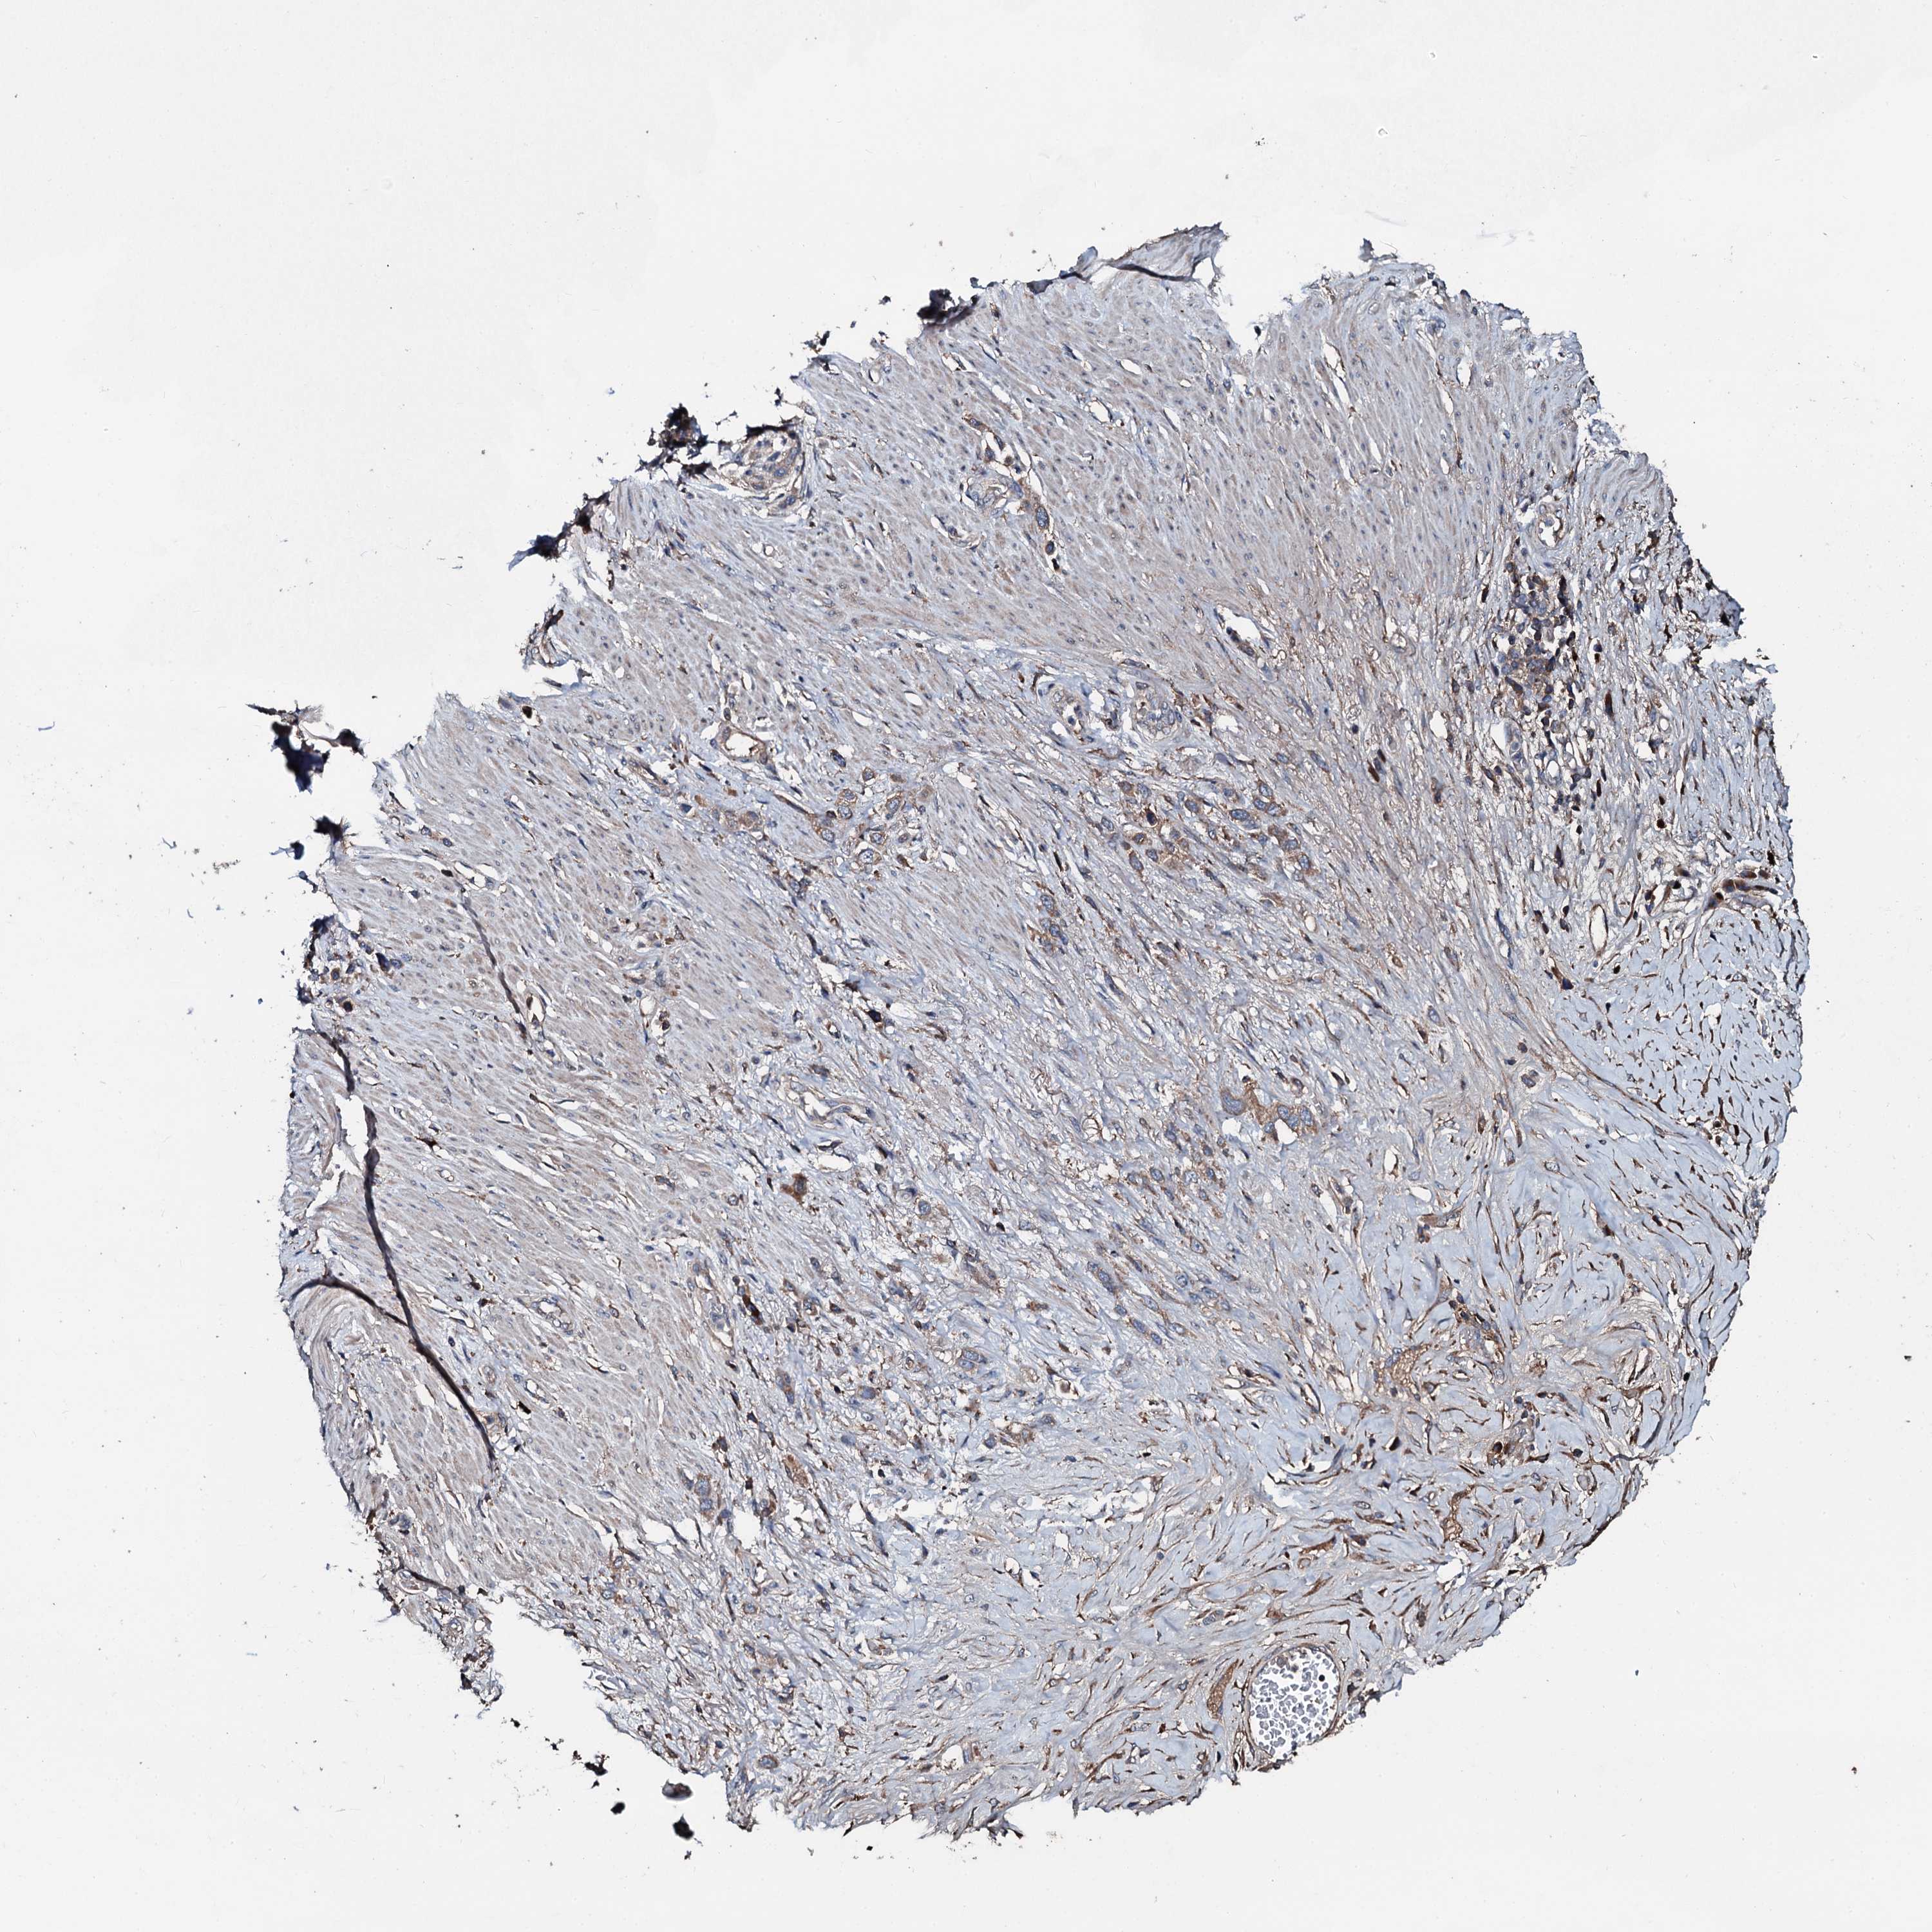

STOMACH CANCER - Protein expressioni

A mouse-over function shows sample information and annotation data. Click on an image to view it in a full screen mode. Samples can be filtered based on level of antibody staining by selecting one or several of the following categories: high, medium, low and not detected. The assay and annotation is described here.

Note that samples used for immunohistochemistry by the Human Protein Atlas do not correspond to samples in the TCGA dataset.

Antibody stainingi

Antibody staining in the annotated cell types in the current human tissue is reported as not detected, low, medium, or high, based on conventional immunohistochemistry profiling in selected tissues. This score is based on the combination of the staining intensity and fraction of stained cells.

Each image is clickable and will lead to virtual microscopy that enables deeper exploration of all samples and also displays staining intensity scores, fraction scores and subcellular localization as well as patient and tissue information for each sample.

Antibody HPA040870

Staining

High

Medium

Low

Not detected

Intensity

Strong

Moderate

Weak

Negative

Quantity

>75%

75%-25%

<25%

None

Location

Nuclear

Cytoplasmic/membranous

Cytoplasmic/membranous,nuclear

Adenocarcinoma, NOS